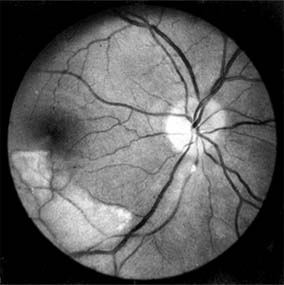

The appearance of the fundus in hypertensive retinopathy is determined by the degree of elevation of the blood pressure and the state of the retinal arterioles. Thus, in young patients with accelerated hypertension, an extensive retinopathy is seen, with hemorrhages, retinal infarcts (cotton-wool spots), choroidal infarcts (Elschnig's spots), and occasionally serous detachment of the retina (Figure 15-10). Severe disk edema is a prominent feature. Vision may be impaired but is restored if blood pressure is reduced with caution.

Figure 15-10

Figure 15-10: Accelerated hypertension. Fluorescein angiogram in a young man showing arteriolar constriction, dilation of capillaries with microaneurysms, and areas of closure. Marked disk edema is present.

In contrast, elderly patients with arteriosclerotic vessels are unable to respond in this manner, and their vessels are thus protected by the arteriosclerosis. It is for this reason that elderly patients seldom exhibit florid hypertensive retinopathy (Figure 15-11).

Figure 15-11

Figure 15-11: Accelerated hypertension. Fluorescein angiogram in an elderly wom.an showing marked arteriolar constriction and irregularity but few signs of florid retinopathy.

Fluorescein angiography has made possible accurate documentation of these microcirculatory changes. In young patients with hypertension, arteriolar attenuation and occlusion are seen, and capillary nonperfusion can be verified in relation to a cotton-wool spot, which is surrounded by abnormal dilated capillaries and microaneurysms with increased permeability on fluorescein angiography.

Resolution of the cotton-wool spots and the arteriolar changes occurs with successful hypotensive therapy. In elderly patients, the underlying arteriosclerotic changes are irreversible.